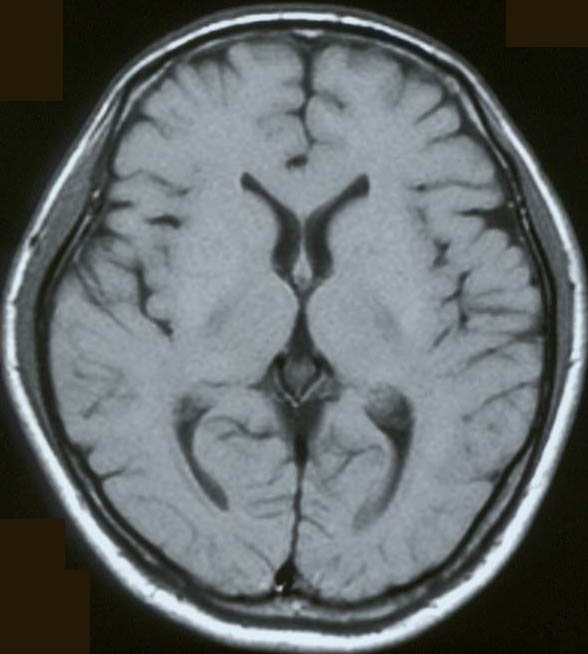

脳の断面(MRI像)

T1強調MRI(左図の7に対応する面) 健康な30歳男性

30歳♂のT1強調MRI画像